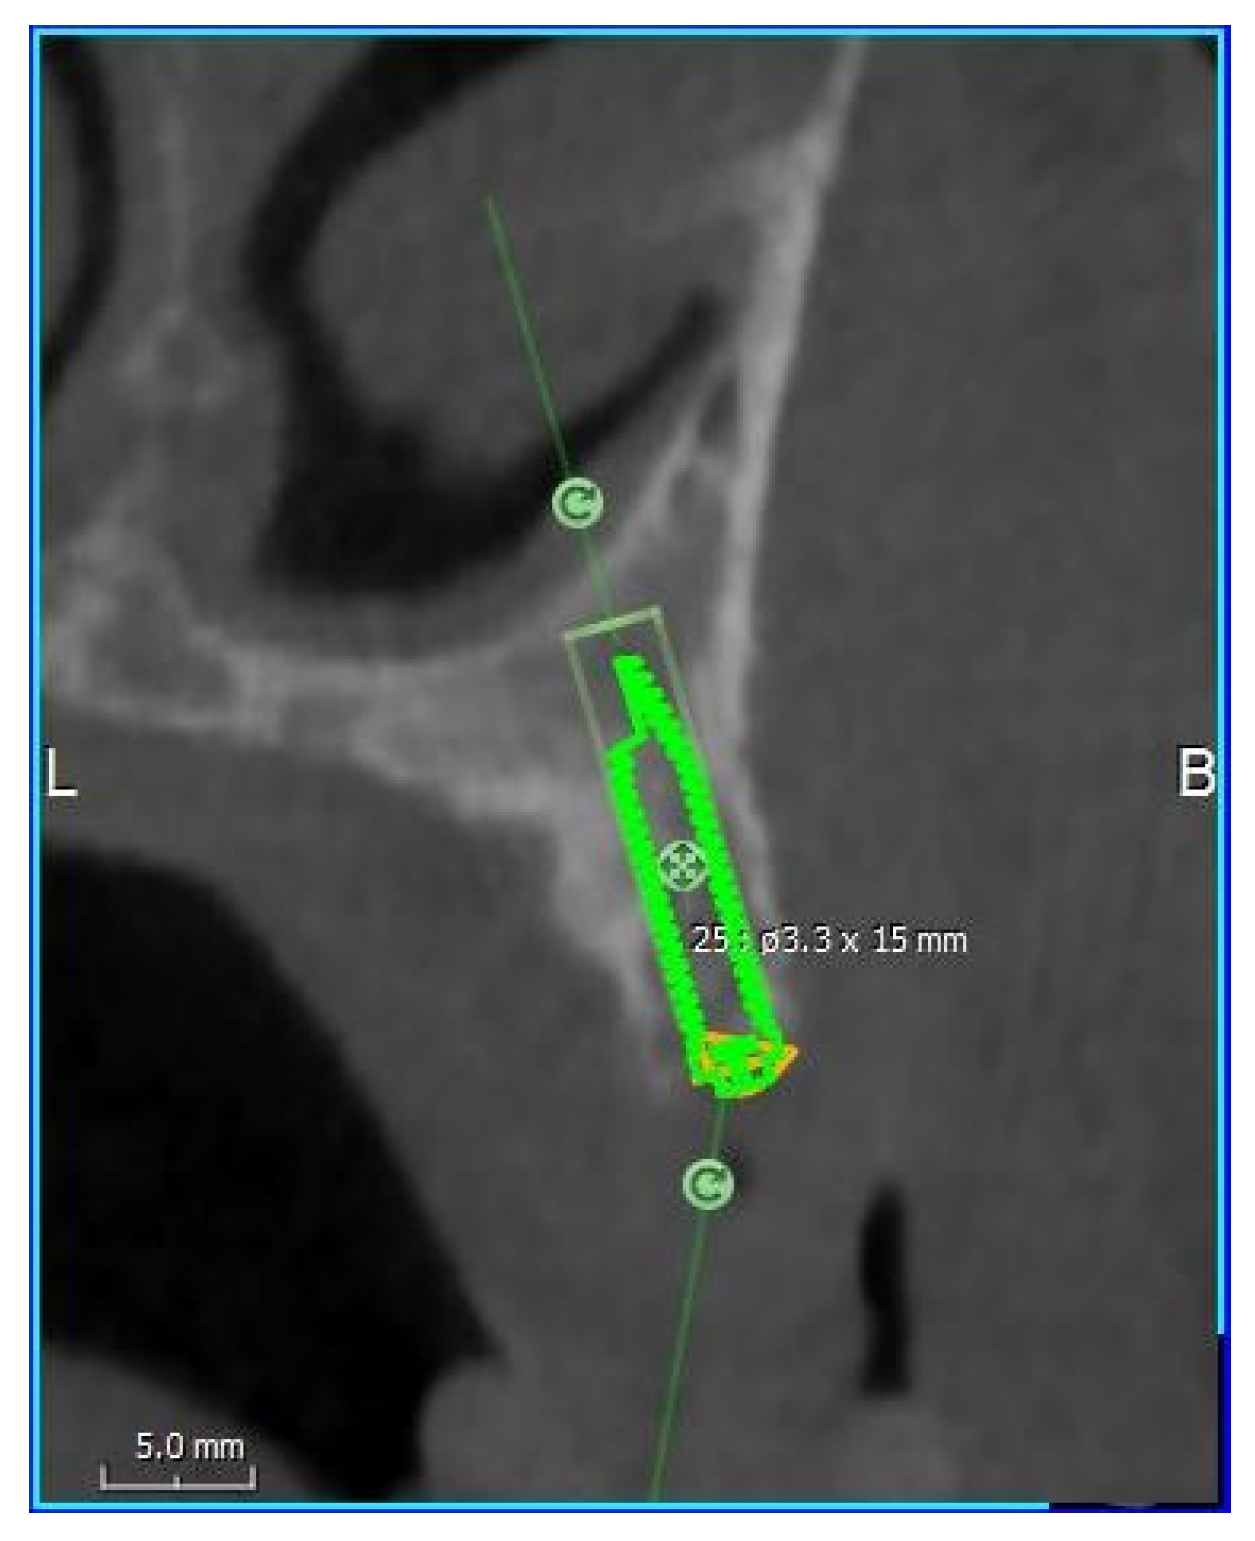

2.2. Virtual Iuxtameatal Implant Positioning

| 30° Tilted Implants | N | Mean | SD | Median | Min | Max | Range |

| Alveolar crest height | 110 | 4.60 | 0.39 | 4.7 | 2.5 | 5 | 2.5 |

| Implant length | 110 | 13.04 | 3,13 | 13.17 | 6.32 | 19.49 | 13.17 |

| Implant diameter | 110 | 3.44 | 0.33 | 3.35 | 2.76 | 4.39 | 1.63 |

| Palatal angle | 110 | 6.30 | 7.28 | 6.80 | −24.27 | 31.52 | 55.79 |

| Bone quality | 110 | 570 | 126.17 | 563.5 | 274 | 934 | 660 |

| 45° Tilted Implants | N | Mean | SD | Median | Min | Max | Range |

| Implant length | 110 | 13.98 | 2.96 | 14.07 | 8.34 | 22.63 | 14.29 |

| Implant diameter | 110 | 3.39 | 0.32 | 3.36 | 2.62 | 4.07 | 1.45 |

| Palatal angle | 110 | 5.25 | 7.13 | 5.87 | −21.19 | 26.72 | 47.91 |

| Bone quality | 110 | 568.86 | 128.22 | 563.5 | 274 | 952 | 678 |